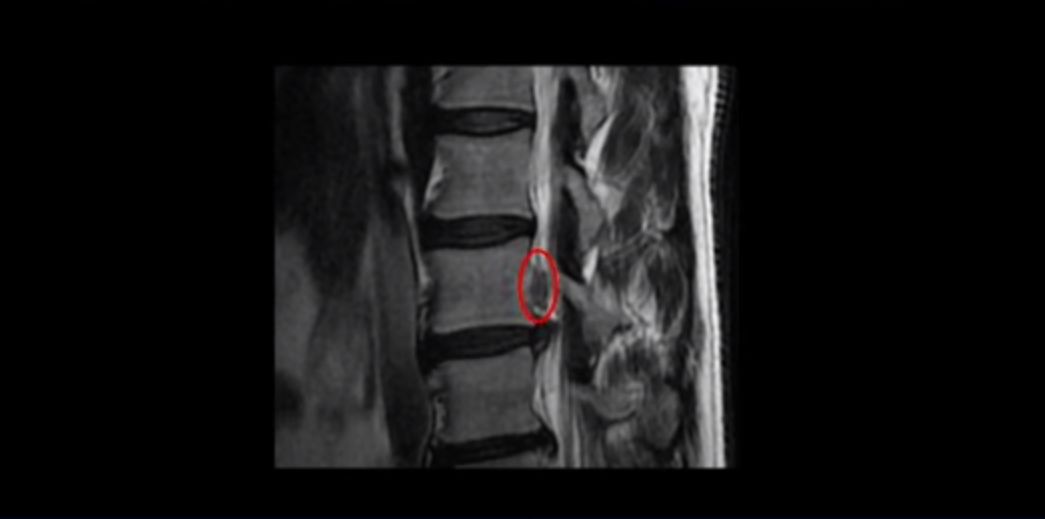

이 환자분 말씀 잘 들으셨습니까? 이분 MRI를 보면 3번과 4번 디스크가 심하게 파열되어 밀려나온 수핵이 위로 밀려 올라가 있습니다. 수핵이 위로 밀려 올라가면서 디스크 본체와의 연결이 끊어져 있습니다.

일반적으로 이런 형태의 밀려나온 수핵이 끊어진 디스크 파열이 훨씬 더 흡수가 잘 됩니다. 그 이유는 뒤에 설명해드리겠습니다.

이분은 오른쪽 허리부터 엉덩이와 허벅지 및 발까지 방사통이 극심하고 감각기능도 떨어졌는데요. 보시다시피 오른쪽 신경 나가는 구멍이 밀려나온 디스크 수핵 때문에 좁아져서 어둡게 보입니다.

그렇다면 이 환자분처럼 심한 디스크 파열이 어떻게 수술 없이 단 몇 주 만에 좋아질 수 있을까요? 디스크 파열이 심하면 우리 몸에서는 밀려나온 디스크 수핵을 이물질로 인식합니다. 이 이물질은 우리 몸에 쓸모 없는 조직이기 때문에 우리 몸의 면역시스템이 염증반응을 통해 녹여서 없애는 것입니다. 그런데 이 환자분처럼 밀려나온 디스크 수핵이 디스크 본체와 아예 분리까지 되어 있으면 우리 몸에서 이물질로 인식될 가능성이 더 높아지겠죠. 그래서 심하게 파열된 디스크일수록 더 흡수가 잘 되는 것이고, 수핵이 끊어진 경우에는 더욱더 흡수가 잘 된다는 겁니다. 따라서 디스크 파열이 심한 환자분들일수록 통증이 극심할 수도 있고 마비가 있을 수도 있지만 비수술치료를 잘 받으면 흡수가 깨끗하게 이루어지고, 따라서 디스크 자연치유가 성공적으로 끝날 가능성이 매우 높습니다. 그렇기 때문에 가능하면 수술을 서두르지 말고 비수술 근육재활치료를 받아보시는 것이 좋다고 말씀 드리는 것입니다.